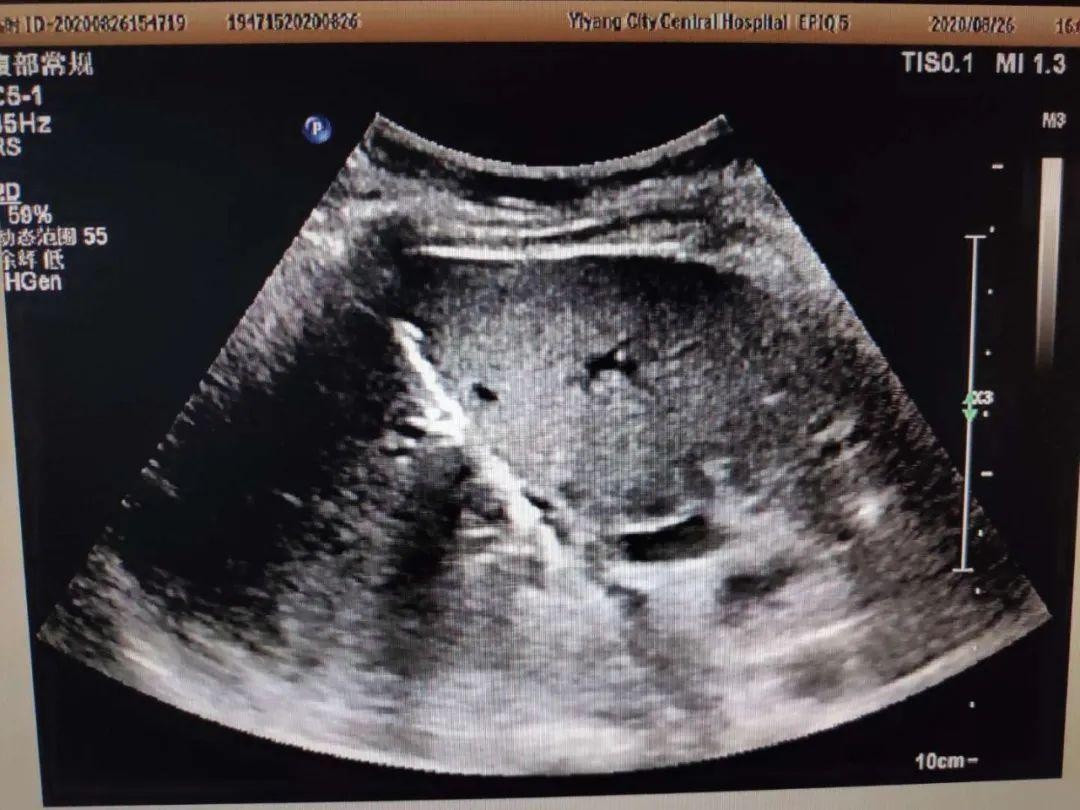

图5经皮经肝胆管穿刺置管引流术

为防止病情进一步加重,需尽早的胆道引流减压,胆道引流减压首先需要减黄。超声科陈锋主任会诊后为刘女士进行了超声引导下经皮经肝胆管穿刺置管引流术(PTCD)。在陈锋主任的指导下江芳强主治医师、李北冰主管护师在超声引导局部麻醉下行经皮经肝胆管穿刺引流术,术后引流通畅,减压减黄明显,刘女士腹痛缓解,全身情况好转,6天后行外科手术,术后一周康复出院。

2、超声引导下经皮穿刺胆囊(PTGD)、肝内胆管(PTCD)置管引流术。